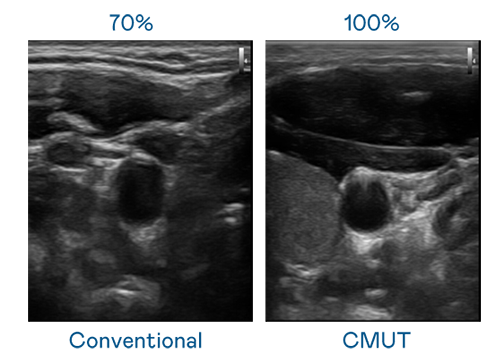

CMUT 技术是一种用电容式微机电元件来产生超音波讯号的技术。与传统 PZT 压电式技术相比,CMUT 频宽增加 30%,更宽频的超音波讯号让影像解析度大幅提升,是实现高影像品质医疗超音波扫描、促进精准医疗发展的关键技术。

大频宽带来超清晰影像

超音波影像的解析度高低,首先取决于探头能发出的讯号频宽。利来w66 CMUT 可提供高清晰的超音波讯号,提供高频宽、高灵敏度、影像纹理细节更高的超音波影像,协助医护人员缩短影像判读时间及利用精准的医疗影像进行诊断。